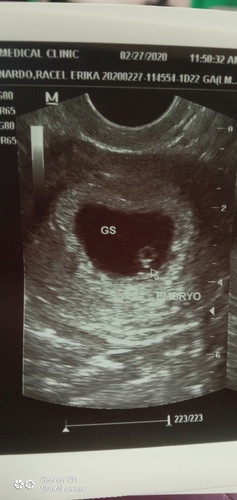

wala pang heart beat si baby

5weeks and 6 days na po akong preggy pero wala pa po heary beat si baby, normal lang ba yun?

May times na hindi pa rinig pag ganyan. Mga 8 to 10 weeks meron na yan

8weeks onwards pa po mommy.